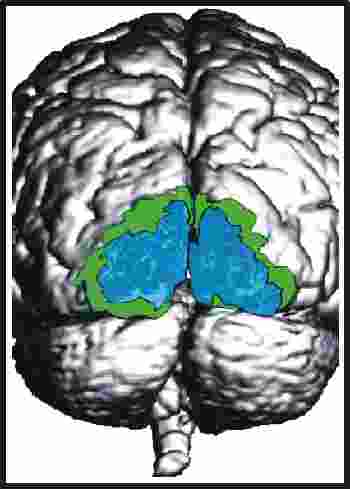

Die funktionellen Daten (bunt) in den beiden Bildern unten wurden mit der funktionellen Kernspintomographie (fNMR) gewonnen, bei der man Änderungen des NMR-Signals bei zunehmender Durchblutung eines aktiven Hirnareals auswertet. Als Beispiele für die Kombination von Bildern sind Überlagerungen von fNMR-Daten mit einem Kernspintomogramm (links) und mit einer graphischen Darstellung des Gehirns (rechts) abgebildet.

Aus: Forschen in Jülich, 1/2000, Forschungszentrum Jülich